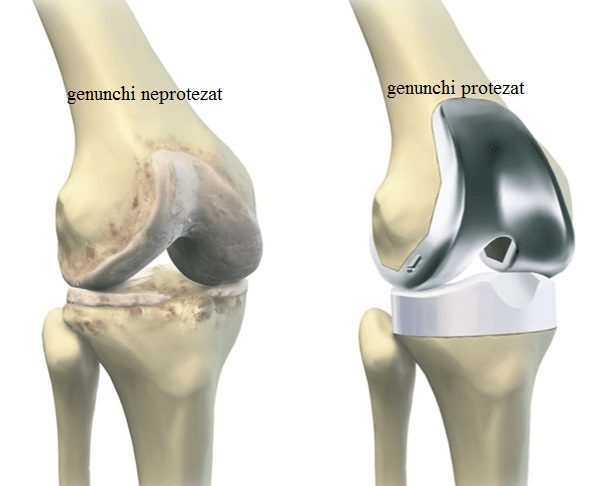

Artroplastia de genunchi reprezintă procedura de implantare a protezei de genunchi. Este o intervenţie standardizată datorită utilizării la o scară largă pe întreg mapamondul şi datorită patologiei frecvent răspândite pentru care este indicată.

Este indicată în principal pentru tratamentul bolii degenerative a genunchiului, şi anume gonartroza (link catre gonartroză), fiind singura procedură ce vindecă boala artrozică în stadii avansate de evoluţie. De asemenea mai are indicaţie şi în patologia tumorală a genunchiului.

Proteza de genunchi este un implant biocompatibil în alcătuirea căruia intră diverse materiale metalice (Titan, Cobalt-Crom şi altele) şi materiale plastice speciale (polietilenă). Componenta metalică a unei proteze intră în contact cu cea alcătuită din polietilenă. Spre deosebire de implanturile folosite la şold, aici nu există o aşa mare diversitate de formă, deoarece prin diverse studii s-a ajuns la o anumită configuraţie a acestei proteze, si anume aceea care tinde să reproducă cel mai bine forma genunchiului, tocmai pentru a păstra biomecanica acestei articulaţii foarte importante în mobilitatea individului. Studiile nu au evidenţiat diferenţe semnificative ale ratei de supravieţuire între diversele tipuri de proteze de genunchi existente pe piaţă, incluzând aici formele de proteze ce păstrează ligamentul încrucişat posterior, cele ce nu-l păstrează, protezele cu platou mobil sau fix, sau recent apărutele proteze personalizate. Acestea din urmă aduc cu siguranţă un beneficiu pacienţilor atunci când sunt bine implantate si bine indicate, dar studiile nu au demonstrat încă o superioritate netă a acestora. Costul de implantare este mult mai mare iar beneficiul adus este, se pare, doar uşor îmbunătăţit faţă de variantele clasice. Desigur, studiile şi îmbunătăţirile viitoare, pot aduce cu siguranţă beneficii mai mari ale acestor tipuri de implanturi. Cel mai folosit tip de implant este proteza de genunchi posterostabilizată, adică cea în care se înlocuieşte ligamentul încrucişat posterior.